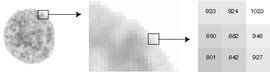

Feulgen-teknikken er en av de mest benyttede cytohistokjemiske fargereaksjoner innen biologi og medisin (1). Teknikken gjør det mulig å spesifikt farge DNA in situ, og er basert på Schiffs eller Schiff-liknende reagensers binding til frigjorte aldehydgrupper fra deoksiribose-molekyler etter HCl-hydrolyse. Fargeintensiteten er proporsjonal med DNA-konsentrasjonen, og mengde DNA i cellekjernen uttrykkes som mengde lys absorbert av Feulgen-fargen over hele cellekjernen (fig 2). Maligne celler karakteriseres ofte av unormalt DNA-innhold, og Feulgen-reaksjonen benyttes i dag til DNA-kvantifisering i cellekjerner for å bestemme DNA-ploidifordelingen i tumorceller.

I en rekke studier sammenliknes DNA-ploidiresultater etter FCM- og ICM-undersøkelser av neoplasier. I 29 studier hvor dette sammenliknes direkte, fant vi en gjennomsnittlig overensstemmelse for de to teknikkene i DNA-ploidiklassifikasjon på 81,6 %. Nær samtlige studier konkluderer med at bildecytometri er en mer spesifikk og sensitiv metode. Bildecytometri har typisk 10 – 20 % flere aneuploide funn enn væskestrømscytometri, samtidig som flere studier indikerer at væskestrømscytometri også kan ha falskt aneuploide funn. Karakteriseringen av falskt positive og falskt negative funn baseres dels på funn i normale og benigne prøver (2 – 4), dels i forhold til andre markører (5 – 11), og endelig i forhold til kjent sykdomsforløp (12 – 17). Forskjellen i analyseresultater kan ha flere årsaker. En meget viktig faktor er at man med bildecytometri har en visuell morfologisk kontroll med hvilke celler som analyseres, noe som sikrer analysens spesifisitet (fig 3). Ved FCM-undersøkelser skiller man vanligvis ikke mellom f.eks. en svulsts epiteliale celler og celler fra omliggende bindevev eller blod. Dette kan gjøres ved såkalt toparameteranalyse med samtidig måling av DNA og f.eks. antistoffer mot cytokeratin, men dette gjøres sjelden i kliniske undersøkelser. En konsekvens av dette er at væskestrømscytometri kan gi et falskt negativt svar (diploid eller euploid) i prøver hvor andelen av aneuploide celler er relativt liten. Et ekstremt eksempel er undersøkelser av lymfeknuter, hvor væskestrømscytometri ofte gir falskt negative (diploide) funn fordi prøven domineres av normale lymfocytter. FCM-an